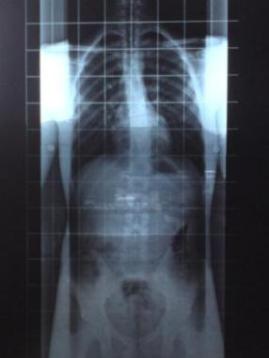

das 3. ist von 2007

thorakal linkskonvex;

ausgemessen wurden ca. 13 grad bws und 6 grad lws.

röngtenbilder schauen nicht dramatisch aus, machen mir aber immense beschwerden, vorallem in der bws und in der lws der ständige "druckschmerz" oberhalb der rechten beckenschaufel.

beachtenswert is irgendwie der untschied bei der lws zw den beiden röngtenganzaufnahmen.